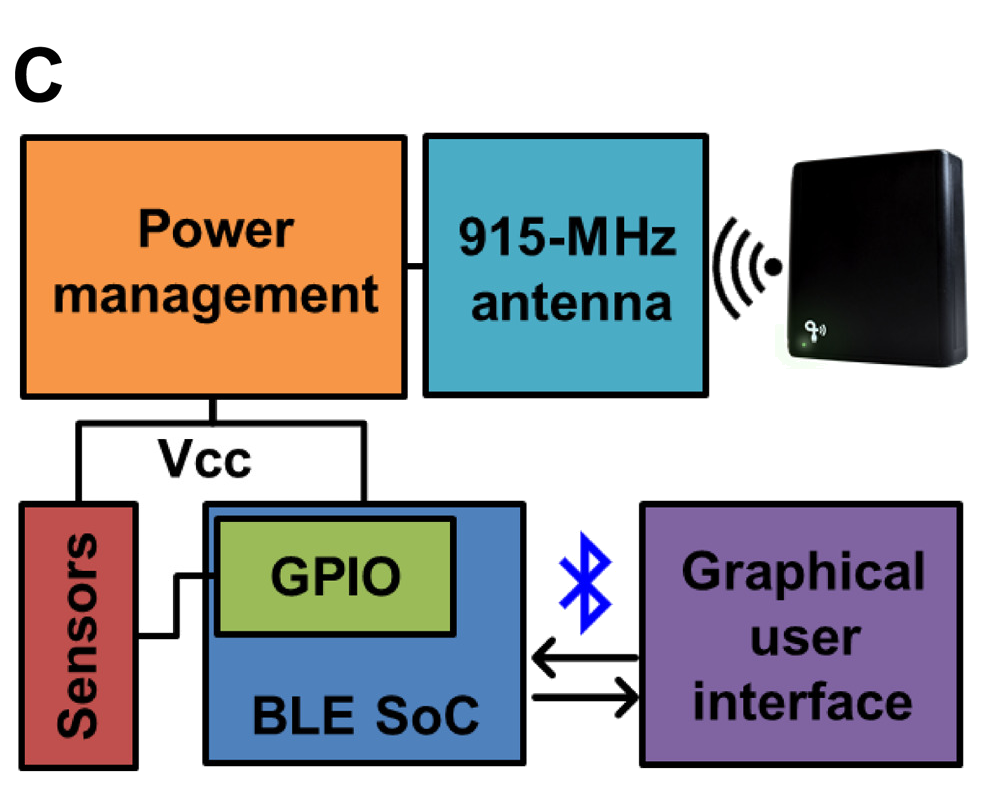

ARTICLE - Biosymbiotic, personalized, and digitally manufactured wireless devices for indefinite collection of high-fidelity biosignals

By TUCKER STUART, KEVIN ALBERT KASPER, CHRISTIAN IWERUNMOR, DYLAN THOMAS MCGUIRE, ROBERTO PERALTA, JESSICA HANNA, MEGAN JOHNSON, MAX FARLEY, THOMAS LAMANTIA, PAUL UDORVICH and PHILIPP GUTRUF | Science Advances | VOL. 7, NO. 41 | Oct 8, 2021

Digital medicine, the ability to stream continuous information from the body to gain insight into health status, manage disease, and predict onset health problems, is only gradually developing. Key technological hurdles that slow the proliferation of this approach are means by which clinical grade biosignals are continuously obtained without frequent user interaction. To overcome these hurdles, solutions in power supply and interface strategies that maintain high-fidelity readouts chronically are critical. This work introduces a previously unexplored class of devices that overcomes the limitations using digital manufacturing to tailor geometry, mechanics, electromagnetics, electronics, and fluidics to create unique personalized devices optimized to the wearer. These elastomeric, three-dimensional printed, and laser-structured constructs, called biosymbiotic devices, enable adhesive-free interfaces and the inclusion of high-performance, far-field energy harvesting to facilitate continuous wireless and battery-free operation of multimodal and multidevice, high-fidelity biosensing in an at-home setting without user interaction.

Video - Prof.Philipp Gutruf presents his lab where has developed 3-D printed, wearable devices that are powered wirelessly and which can seamlessly integrate with the shape of an individual’s body at Biomedical Engineering at the University of Arizona. The Lab is on the forefront of designing the next generation of biomedical devices for monitoring users’ health.

By TUCKER STUART, KEVIN ALBERT KASPER, CHRISTIAN IWERUNMOR, DYLAN THOMAS MCGUIRE, ROBERTO PERALTA, JESSICA HANNA, MEGAN JOHNSON, MAX FARLEY, THOMAS LAMANTIA, PAUL UDORVICH and PHILIPP GUTRUF | Science Advances | VOL. 7, NO. 41 | Oct 8, 2021

Digital medicine, the ability to stream continuous information from the body to gain insight into health status, manage disease, and predict onset health problems, is only gradually developing. Key technological hurdles that slow the proliferation of this approach are means by which clinical grade biosignals are continuously obtained without frequent user interaction. To overcome these hurdles, solutions in power supply and interface strategies that maintain high-fidelity readouts chronically are critical. This work introduces a previously unexplored class of devices that overcomes the limitations using digital manufacturing to tailor geometry, mechanics, electromagnetics, electronics, and fluidics to create unique personalized devices optimized to the wearer. These elastomeric, three-dimensional printed, and laser-structured constructs, called biosymbiotic devices, enable adhesive-free interfaces and the inclusion of high-performance, far-field energy harvesting to facilitate continuous wireless and battery-free operation of multimodal and multidevice, high-fidelity biosensing in an at-home setting without user interaction.

Video - Prof.Philipp Gutruf presents his lab where has developed 3-D printed, wearable devices that are powered wirelessly and which can seamlessly integrate with the shape of an individual’s body at Biomedical Engineering at the University of Arizona. The Lab is on the forefront of designing the next generation of biomedical devices for monitoring users’ health.